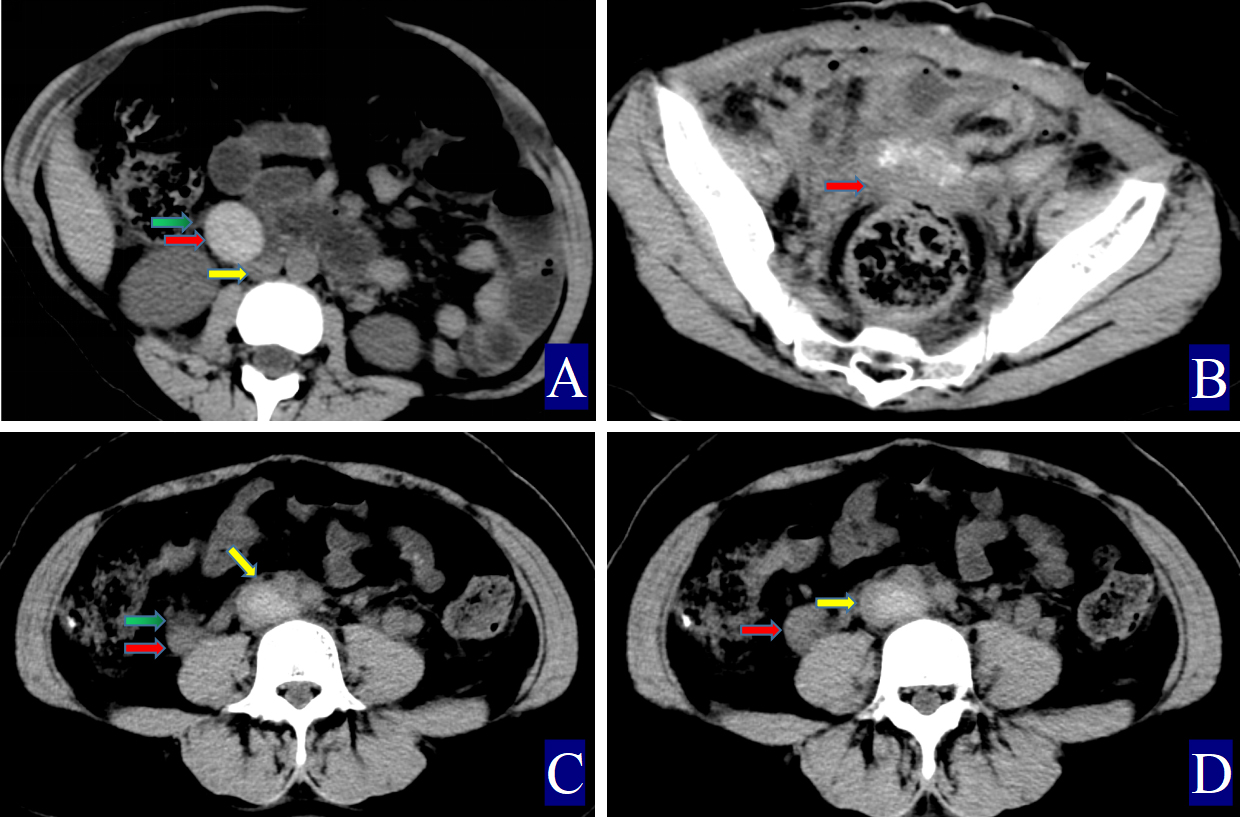

Fig. 3. The primary and secondary CT findings of ovarian vein thrombophlebitis. The red arrow indicates the ovarian vein, the yellow arrow indicates the inferior vena cava, and the green arrow indicates the periovarian vein exudate. (A) Non-contrast axial CT image. The right ovarian vein is approximately 2.92 cm wide (CT value = 63.50 HU, red arrow). The CT value of the inferior vena cava is 38.40 HU (yellow arrow), with adjacent exudation (green arrow). (B) Non-contrast axial CT image showing pelvic effusion (thick red arrow). (C,D) A 21-year-old woman with right ovarian vein thrombophlebitis and inferior vena cava thrombosi: (C) Non-contrast axial CT image. The right ovarian vein is about 1.6 cm wide (CT value = 59.30 HU, red arrow). The inferior vena cava shows a CT value of 71.80 HU (yellow arrow), and surrounding exudation is noted (green arrow). (D) Non-contrast axial CT image.

The primary CT findings of POVT included filling defects within the ovarian vein lumen along with thickening of the vessel wall (Figs. 1,2,3). Secondary signs involved pelvic effusion in 13 cases and periovarian venous exudation with increased fat density in 19 cases (Figs. 1A,C,3A,C). One patient, who developed extensive thrombosis extending to both lower extremity veins, the inferior vena cava, and pulmonary arteries, died from postpartum hemorrhagic shock. The remaining 23 patients fully recovered.

Compared with the non-POVT group, the POVT group showed significantly greater ovarian vein width on the thrombus side, higher CT attenuation of the thrombus-side ovarian vein, as well as increased CT attenuation difference and ratios (p = 0.001, Figs. 1,2,3). Using 0.90 cm as the cut-off value for ovarian vein width, the sensitivity reached approximately 91.70%, with a specificity of 95.20% (Figs. 1A,2A,3A,C,D). With 46.00 HU as the threshold for ovarian vein CT value on the thrombus side, both sensitivity and specificity were 100% (Figs. 1A,2A,3A). For a CT attenuation difference cut-off of 12.50 HU, the sensitivity was 95.30%, and specificity remained 100%. Similarly, a ratio cut-off of 1.1 yielded a sensitivity of 95.30% and specificity of 100% (Figs. 1A,2A,3A).

In one POVT case involving extensive inferior vena cava thrombosis, the CT value of the inferior vena cava exceeded that of the ovarian vein, resulting in a negative CT attenuation difference of –12.50 HU and a ratio of 0.83 (Table 1; Fig. 3C,D).

Direct signs observed on CT included variable widening of the ovarian vein, increased intraluminal density, and filling defects, often accompanied by vessel wall thickening, which is in line with prior reports [16, 17, 18, 19, 20, 21] (Figs. 1,2,3). A notable finding in our study was the identification of previously undescribed indirect signs: increased fat density around the ovarian vein in the pelvis and the presence of small-volume pelvic effusion (Figs. 1A,3A–D). These signs may reflect the local inflammatory reaction associated with thrombophlebitis.

Semi-quantitative parameters from non-contrast CT scans revealed clear differences between the POVT and non-POVT groups. The thrombus-side ovarian vein width, CT attenuation of the thrombotic ovarian vein, the difference between ovarian and inferior vena cava CT values, and their ratio were all significantly higher in the POVT group (p = 0.001, Figs. 1,2,3). These parameters may serve as reliable diagnostic references. For instance, using 0.90 cm as the cut-off for ovarian vein width yielded a sensitivity of approximately 91.70% and a specificity of 95.20%. This supports earlier findings [5] that vein enlargement is a key feature of POVT (Figs. 1,2,3). A CT attenuation cut-off of 46.00 HU for the thrombotic ovarian vein achieved 100% sensitivity and 100% specificity (Figs. 1,2,3). Similarly, a CT attenuation difference threshold of 12.50 HU and a ratio cut-off of 1.1 also demonstrated strong diagnostic performance (Figs. 1,2,3). However, in one patient with extensive thrombosis of the inferior vena cava, the ovarian vein had a lower CT value than the cava, resulting in a negative difference (–12.50 HU) and a ratio of 0.83, reflecting variability in advanced or complex cases. Currently available non-invasive diagnostic tools for POVT include Doppler ultrasound (sensitivity 52%), magnetic resonance imaging (MRI) (92%), and contrast-enhanced multidetector CT (100%) [5]. The present study indicates that non-contrast CT semi-quantitative parameters can closely match the diagnostic accuracy of enhanced CT, while offering greater simplicity, lower cost, and avoiding the risks associated with contrast agent use.